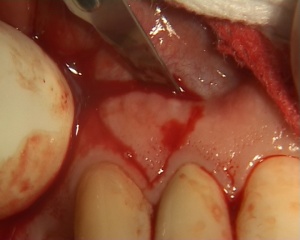

Supression d'un frein entre 11 et 21. Afin d'obtenir un meilleur rendu esthétique, un greffon est prélevé au niveau de la gencive vestibulaire, entre 12 et 13 et mis en place sur le site receveur.

Photos extraites de la vidéo :